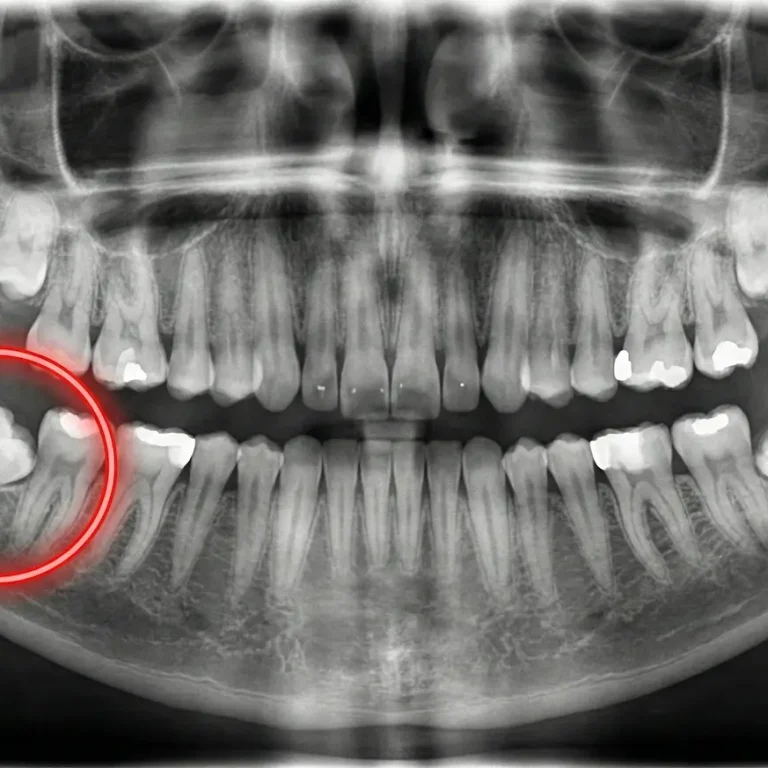

Genellikle 17 ile 25 yaşları arasında sürmeye başladığı için "20 yaş dişleri" (akıl dişleri) olarak adlandırılan bu dişler, …